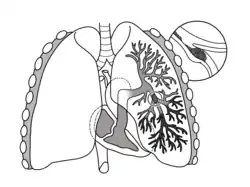

![]() رسم توضيحي للرئة يصور الانصمام الرئوي على أنه خثرة (جلطة دموية) انتقلت من منطقة أخرى من الجسم، مسببة انسداد الشريان الرئوي القصبي، مما يؤدي إلى خثار شرياني من الفصوص العلوية والسفلية في الرئة اليسرى رسم توضيحي للرئة يصور الانصمام الرئوي على أنه خثرة (جلطة دموية) انتقلت من منطقة أخرى من الجسم، مسببة انسداد الشريان الرئوي القصبي، مما يؤدي إلى خثار شرياني من الفصوص العلوية والسفلية في الرئة اليسرى | |